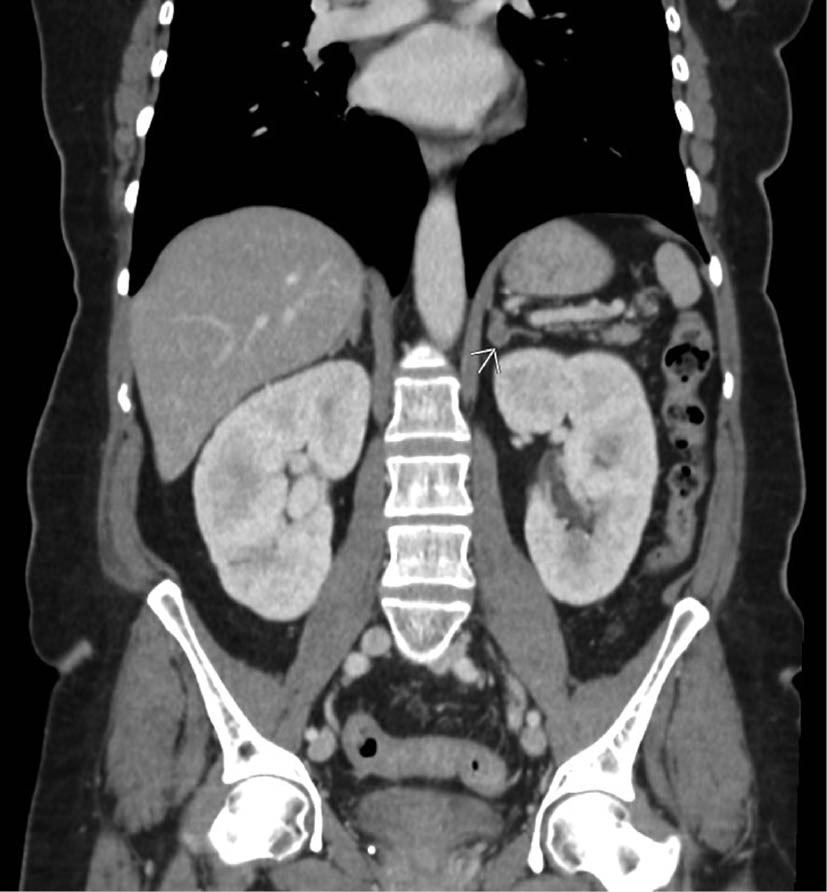

Conn's Syndrome

- benign adenoma of the zona glomerulosa of the adrenal cortex

- rarely due to bilateral hyperplasia or carcinoma